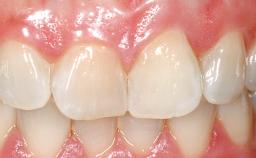

Late Placement of an Implant in a Maxillary Left Central Incisor Site

On examination, the patient had a low lip line and only displayed the coronal half of the anterior teeth when smiling.

Prosthodontic SAC classification

| SAC Level | Advanced |

| Defining Characteristics | One missing tooth to be replaced by an implant-borne crown |

| Esthetic Risk | Medium |